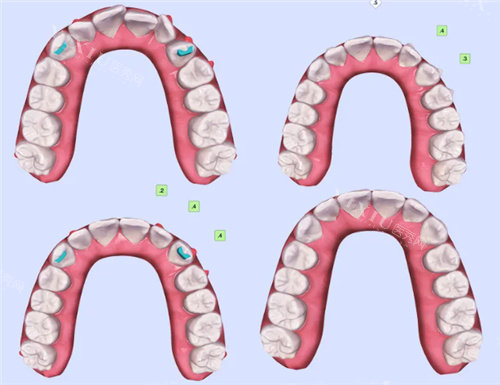

自锁牙套宛如科技感十足的未来产物。它采用了独特的自锁托槽设计,托槽上配备了滑盖或弹簧夹装置,能够直接将弓丝稳稳地锁在托槽的槽沟内,无需借助额外的结扎丝或橡皮圈。这种设计大大减少了弓丝与托槽之间的机械摩擦,使得牙齿移动的阻力降低了约 30%。像 DamonQ、SmartClip 和 In - Ovation 等都是典型的自锁牙套品牌。

而非自锁牙套则更像是传统的工匠之作。它依赖金属结扎丝或橡皮圈来固定弓丝,金属结扎丝有时可能会刺激口腔黏膜。传统金属托槽需要缠绕结扎丝,陶瓷托槽常用透明橡皮圈,操作相对复杂,而且结扎物还可能因老化而增加复诊的需求。